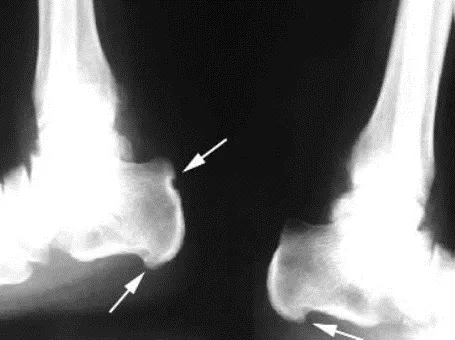

Дактилит (воспаление пальца/пальцев) возникает в результате одновременного поражения сухожилий сгибателей и/или разгибателей пальцев и артрита межфаланговых суставов. Клинически проявляется болью, цианотично-багровым окрашиванием кожных покровов, плотным отеком всего пальца, болевым ограничением сгибания, формируется характерная для ПсА «сосискообразная» деформация пальца.

Энтезит клинически проявляется болью, иногда припухлостью в точках энтезов. Локализация - верхний край надколенника, края (крылья) подвздошных костей, трохантеры, место прикрепления ахиллова сухожилия и подошвенного апоневроза к пяточной кости, латеральный надмыщелок плечевой кости, медиальный мыщелок бедренной кости. Энтезиты пяточных областей часто являются причиной снижения функциональных возможностей больных.

Рисунок 9. Энтезит при псориатическом артрите. Ахиллобурсит левой стопы – припухание в области прикрепления ахиллова сухожилия к заднему краю пяточной кости

Рисунок 13. Рентгенограмма пяточных областей в боковой проекции при псориатическом артрите. Видны энтезофиты в области плантарной фасции, эрозия задней поверхности пяточного бугра (стрелки).

Диагностика